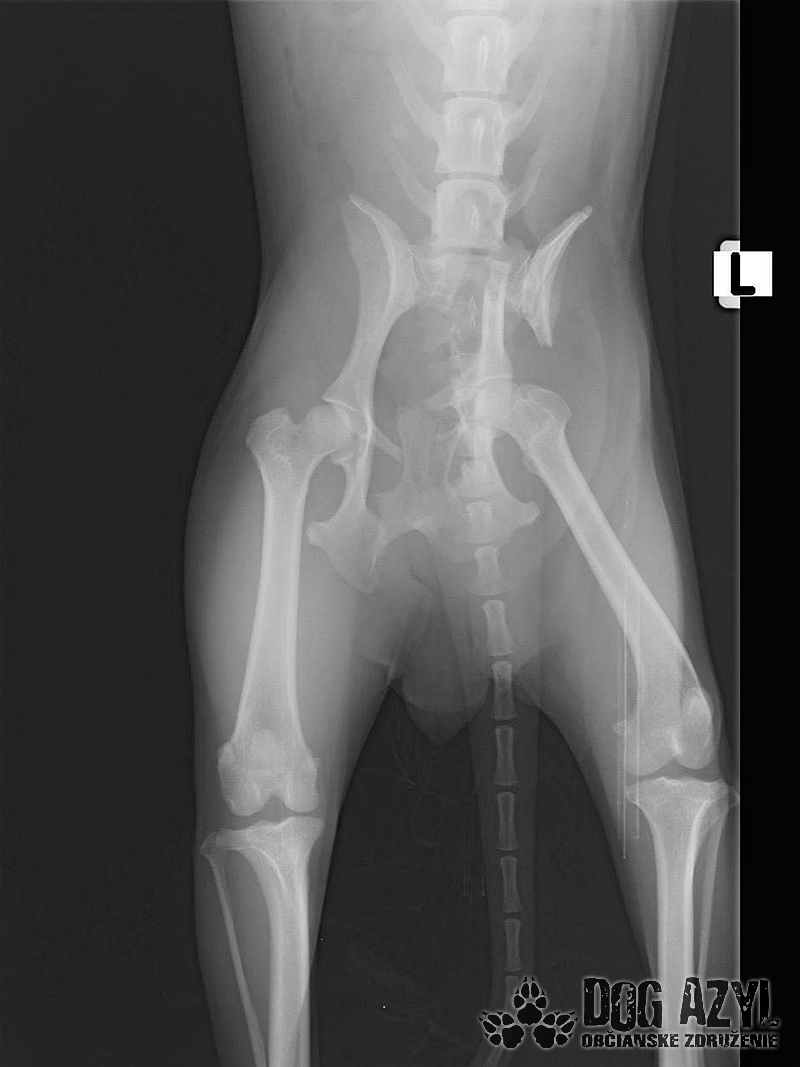

Bola neskutočne zanedbaná, hladná a dolámaná. Panvu má zlomenú na troch miestach, od úderu jej praskol močový mechúr a mala na sebe snáď všetky blchy sveta, žrali ju zaživa. Zotavuje sa.. Pomaličky, ale zotavuje sa po náročných operáciách a dúfame, že bude opäť v poriadku. Bude potrebovať rehabilitovať, aby vedela opäť behať, ale zabezpečíme jej úplne všetko, čo bude treba!!